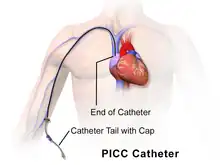

A peripherally inserted central catheter (PICC or PICC line), less commonly called a percutaneous indwelling central catheter, is a form of intravenous access that can be used for a prolonged period of time (e.g., for long chemotherapy regimens, extended antibiotic therapy, or total parenteral nutrition) or for administration of substances that should not be done peripherally (e.g., antihypotensive agents a.k.a. pressors). It is a catheter that enters the body through the skin (percutaneously) at a peripheral site, extends to the superior vena cava (a central venous trunk), and stays in place (dwells within the veins) for days, weeks or even months.

A PICC is inserted in a peripheral vein such as the cephalic vein, basilic vein or brachial vein in the arm, and then threaded through the veins toward the heart, until the end of the catheter rests in the proximal superior vena cava or cavoatrial junction. They must be inserted by a trained medical professional, including a physician, but also any trained medical professional such as a specially trained registered nurse.[5] An ultrasound or chest X-ray, or the use of fluoroscopy, can be used during insertion and to confirm placement. The insertion is a sterile procedure, but does not need to be performed in a completely sterile environment like an operating room.